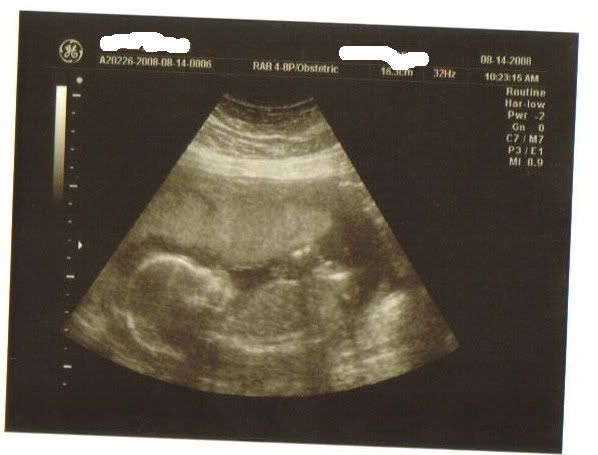

Here he is